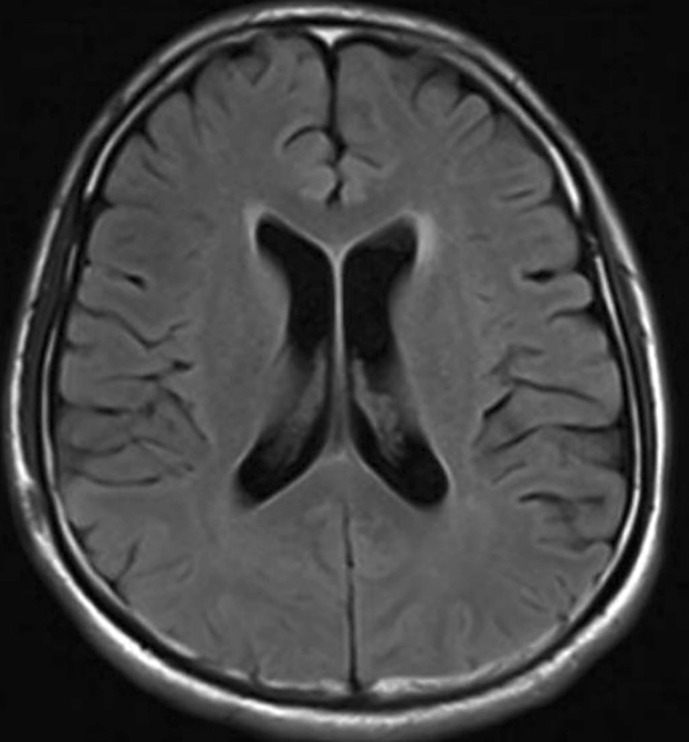

Case presentation: A 31-year-old Asian male patient suffering from epileptic onset and poor antiepileptic treatment was demonstrated. The spinal imaging examination was performed, and the patient suffered a space-occupying lesion within the conus medullaris related to spinal deformity, spinal embolism, etc. The autoimmune encephalitis spectrum revealed mGluR5 antibody IgG (+) 1:10 response. The patient stabilized after treatment with hormones and human immunoglobulin. Some hair and lipid droplets could be observed in the dural sac intraoperatively, and more hair and lipid-like material were present in the spinal cord. Postoperative pathology established the diagnosis as a conus medullaris teratoma in adults. Epileptic seizures stopped after surgery, and no additional seizures were reported during the 33-month follow-up period.